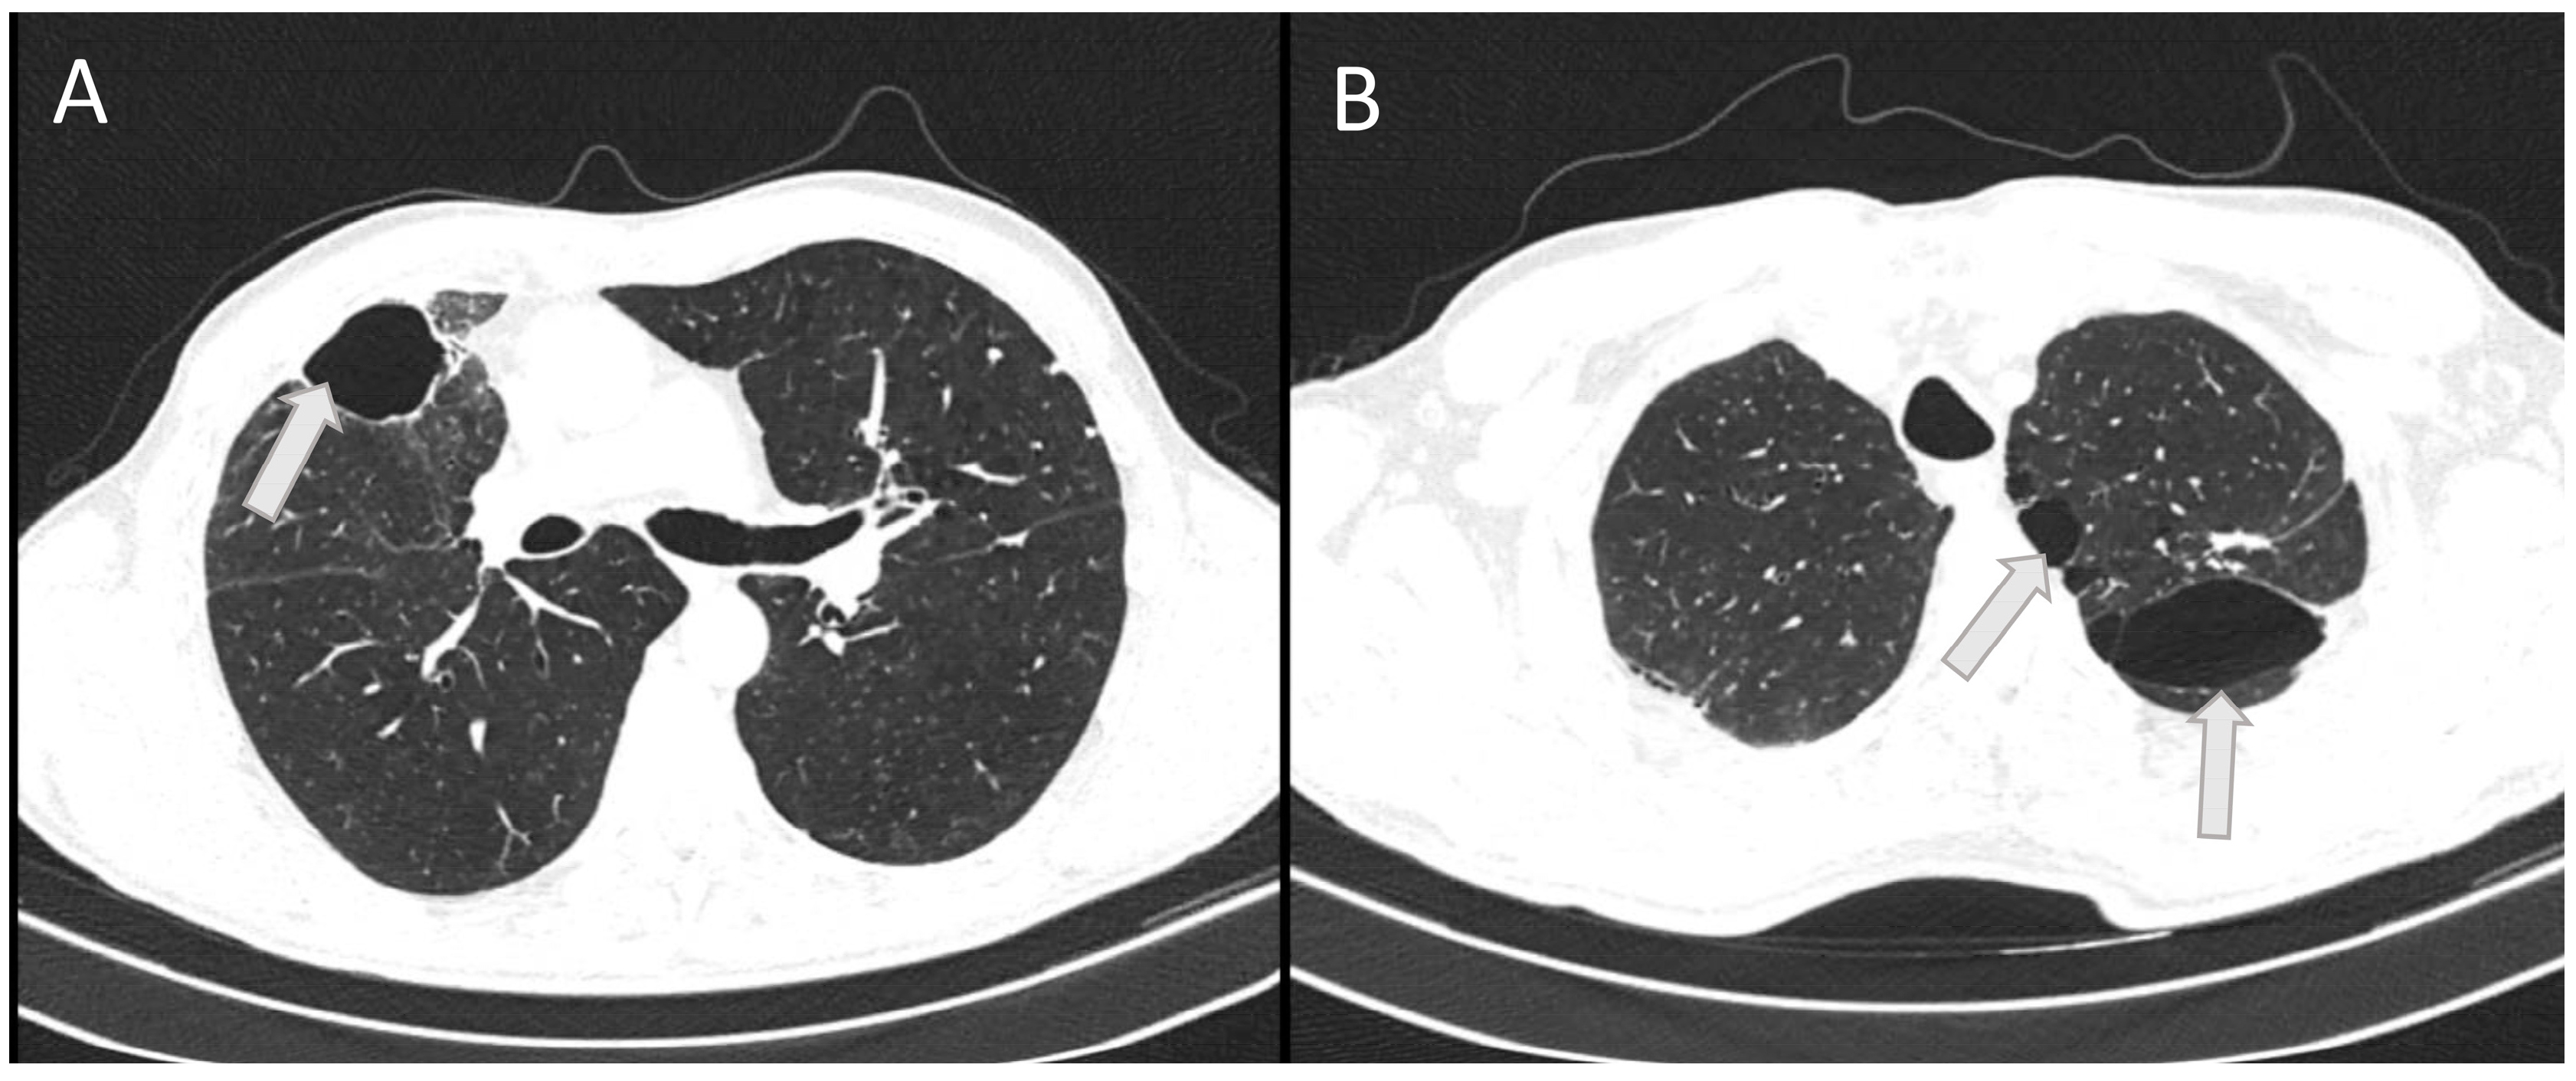

On this outpatient examination, a CT scan of the lung was performed, which confirmed bullous changes in the left side of the lung (Figure 4). Subjectively, he had discomfort when breathing and pain in the right chest. He complained about poor physical condition. His medical therapy prescribed by a pulmonologist was ipratropium bromide (Atrovent N, Boehringer Ingelheim Pharma GmbH & Co., Ingelheim, Germany) 3 × 2 breaths.

Figure 4. The horizontal CT scan section at the level of the 6th thoracic vertebra (A) and at the level of the 3rd thoracic vertebra (B) showing residual bullous changes (arrows) 6 months after severe chest injury with bilateral pneumonia in a 53-year-old patient.

High ventilation pressures can improve oxygenation but may increase the risk of barotrauma in the healthy lung. Due to lower resistance, a larger volume of inhaled gas will be directed to healthy areas of the lungs [17]. This is the reason why the strongest bullous changes after mechanical ventilation in our patient were found on the follow-up CT after discharge in the lung areas that were less affected by trauma and inflammation, i.e., in the upper left lung lobe.